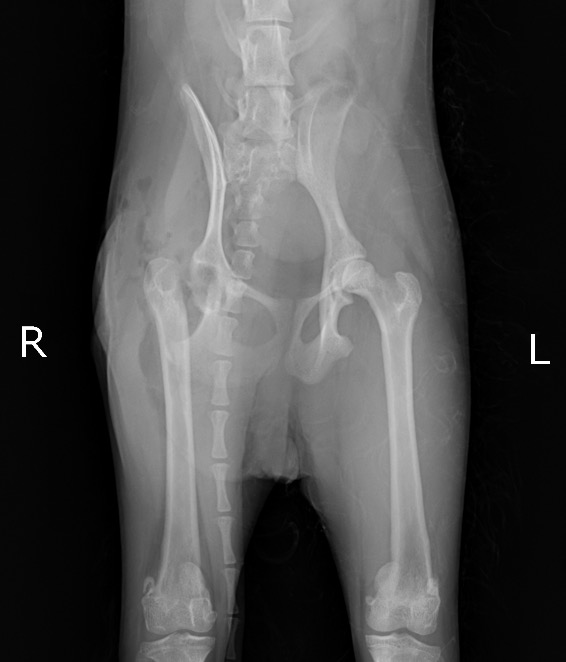

術後X線